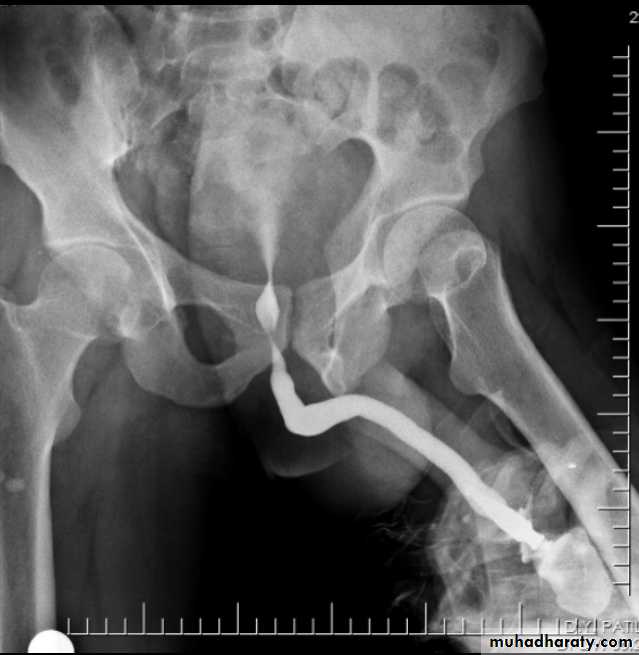

Ascending or retrograde urethrogram

Best to visualize and assess the anterior urethra